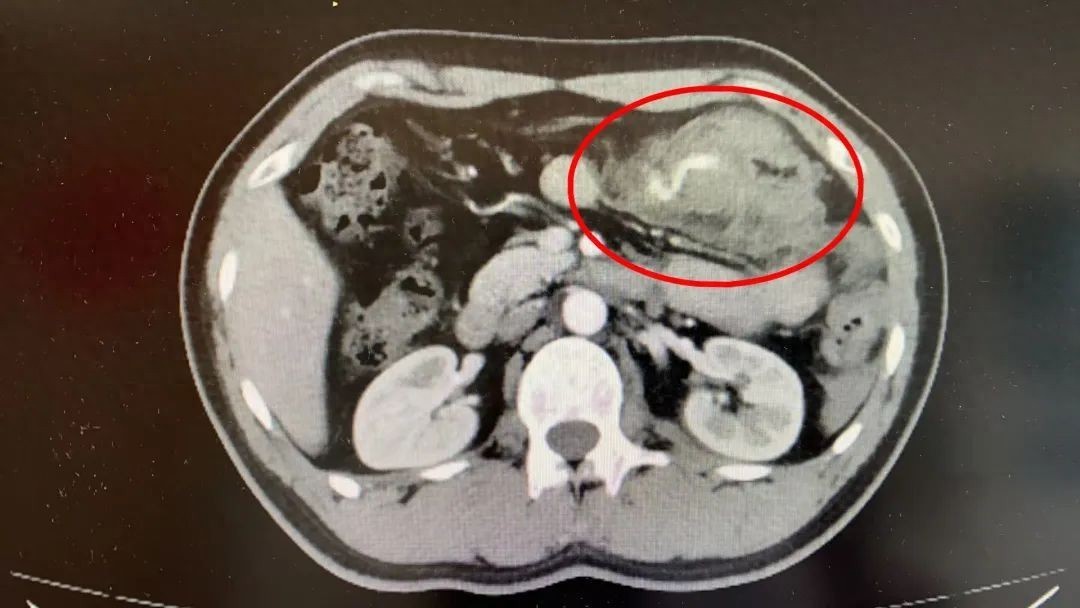

救护车的呼啸声划破寂静,34岁陈先生因车祸被送至杭州市一医院瓶窑院区(余杭三院)紧急抢救。腹腔出血 病情急转直下“刚才肚子很痛,现在已经好多了”,入院时陈先生神志清醒,生命体征平稳,能够清楚和急诊医护人员交流。急诊医护人员查体发现陈先生没有明显伤口。凭借多年的临床经验,急诊医生为排除腹腔内出血的可能性,于是进一步完善腹部CT检查,检查结果发现陈先生左上腹有团片状高密度影,B超提示腹腔积液已有2cm,证实了医生的猜测。此时,陈先生血压开始下降,收缩压从125mmHg下降至105mmHg,舒张压从90mmHg下降至80mmHg,病情急转直下。